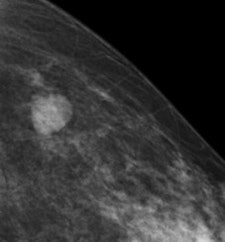

With tomosynthesis, low-dose images are obtained over a limited arc, and the projections are mathematically reconstructed into a series of sections with the hope that specificity and sensitivity will be improved. Initial work using tomosynthesis as an add-on to conventional 2D mammography suggested the potential for substantial improvements in specificity, the authors noted. They compared the diagnostic accuracy of 2D digital mammography with that of two-view (mediolateral and craniocaudal) and single-view (mediolateral oblique) tomosynthesis in an observer study involving two institutions: Cambridge and Capio St Göran's Hospital in Stockholm.

Ten accredited readers classified 130 women with breast density of 2 to 4 using 2D mammography and two-view tomosynthesis. Another 10 reviewed the same cases using 2D mammography but with single-view tomosynthesis.

For diagnostic accuracy, 2D mammography performed significantly worse than two-view tomosynthesis (average area under receiver operating characteristic curve [AUC] = 0.772 for 2D, AUC = 0.851 for tomosynthesis; p = 0.021). The researchers found significant differences for masses and microcalcification (p = 0.037 and 0.049, respectively). The difference in AUC between the two modalities was significant only for the five readers with the least amount of experience (p = 0.03 versus p = 0.25 for readers with 10 or more years of experience). No significant difference was seen in reader performance when 2D mammography was compared with single-view tomosynthesis.